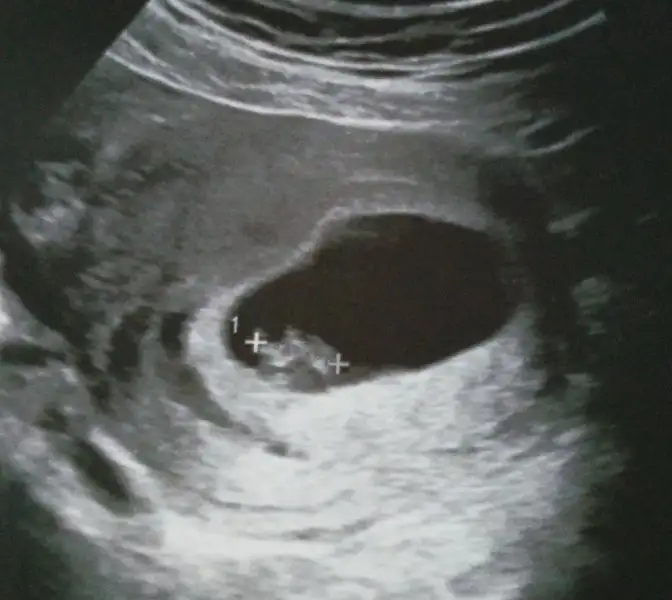

Merhabalar bende bı tahmin alabilirmiyim acaba 7. Hafta 10.hafta ve 12.hafta ultrason fotolarina bakarmisiniz benim ikinci bebeğim kızımın ultrason fotolarina bakıyorum bu bebeğim çok farklı acaba cinsiyet farklimi ki nuba göre bakıyorum ama anlayamadım bi anlayan arkadaşlardan rica ediyorum